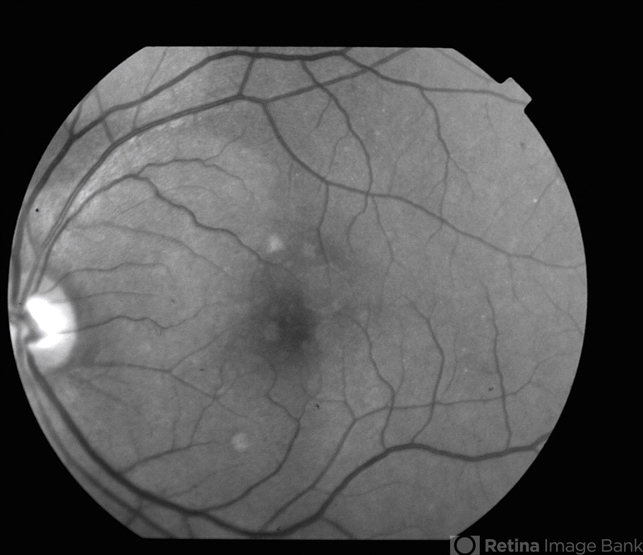

- Choroidal Hemangioma

- choroidal hemangioma, choroidal tumor, red-free

- Red-free photography reveals a 2 x 3 DD well circumscribed lesion superior nasal to the fovea.